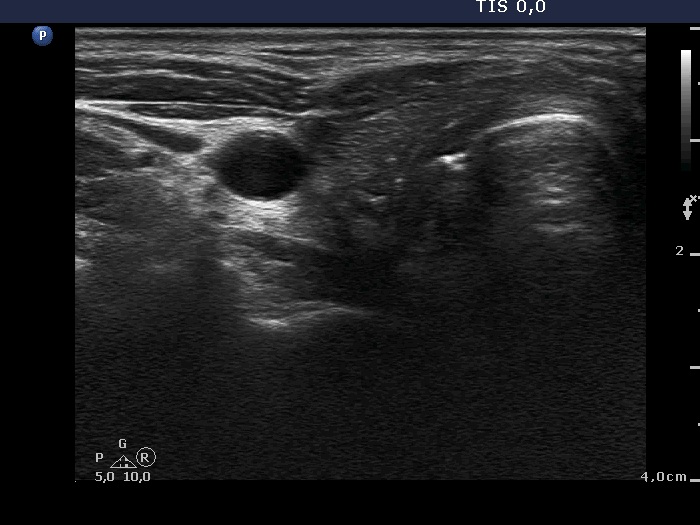

One month after surgery (second row of images):

Clinical data: The patient had no complaints.

Palpation: There was a relatively large, painless mass in the left thyroid bed.

Result of blood test: euthyroidism on daily 125 microgram levothyroxine (TSH 0.87 mIU/L).

Ultrasonography. The thyroid parenchyma was replaced by regenerative tissue. There was a cystic lesion in the left thyroid bed with a maximal diameter of 23 mm.